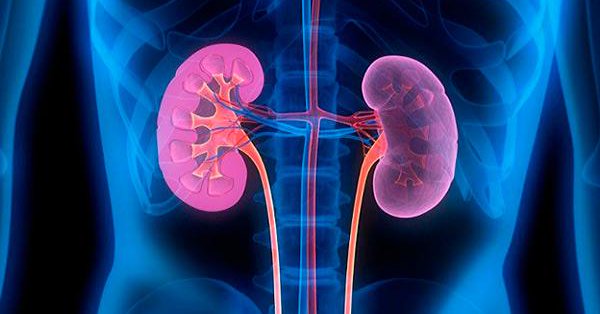

Uso de inhibidores de la bomba de protones y el riesgo de lesión renal aguda en pacientes con artritis reumatoide: estudio de cohortes

03 agosto 2018

Drug Saf, agosto de 2018 Este estudio de cohorte entre pacientes con artritis reumatoide encontró un riesgo significativamente mayor de lesión renal aguda asociada con el uso de inhibidores de la bomba de protones. Estos hallazgos pueden ayudar a informar la toma de decisiones clínicas cuando se consideran los riesgos y beneficios del tratamiento con inhibidores de la bomba de protones en la artritis reumatoide.